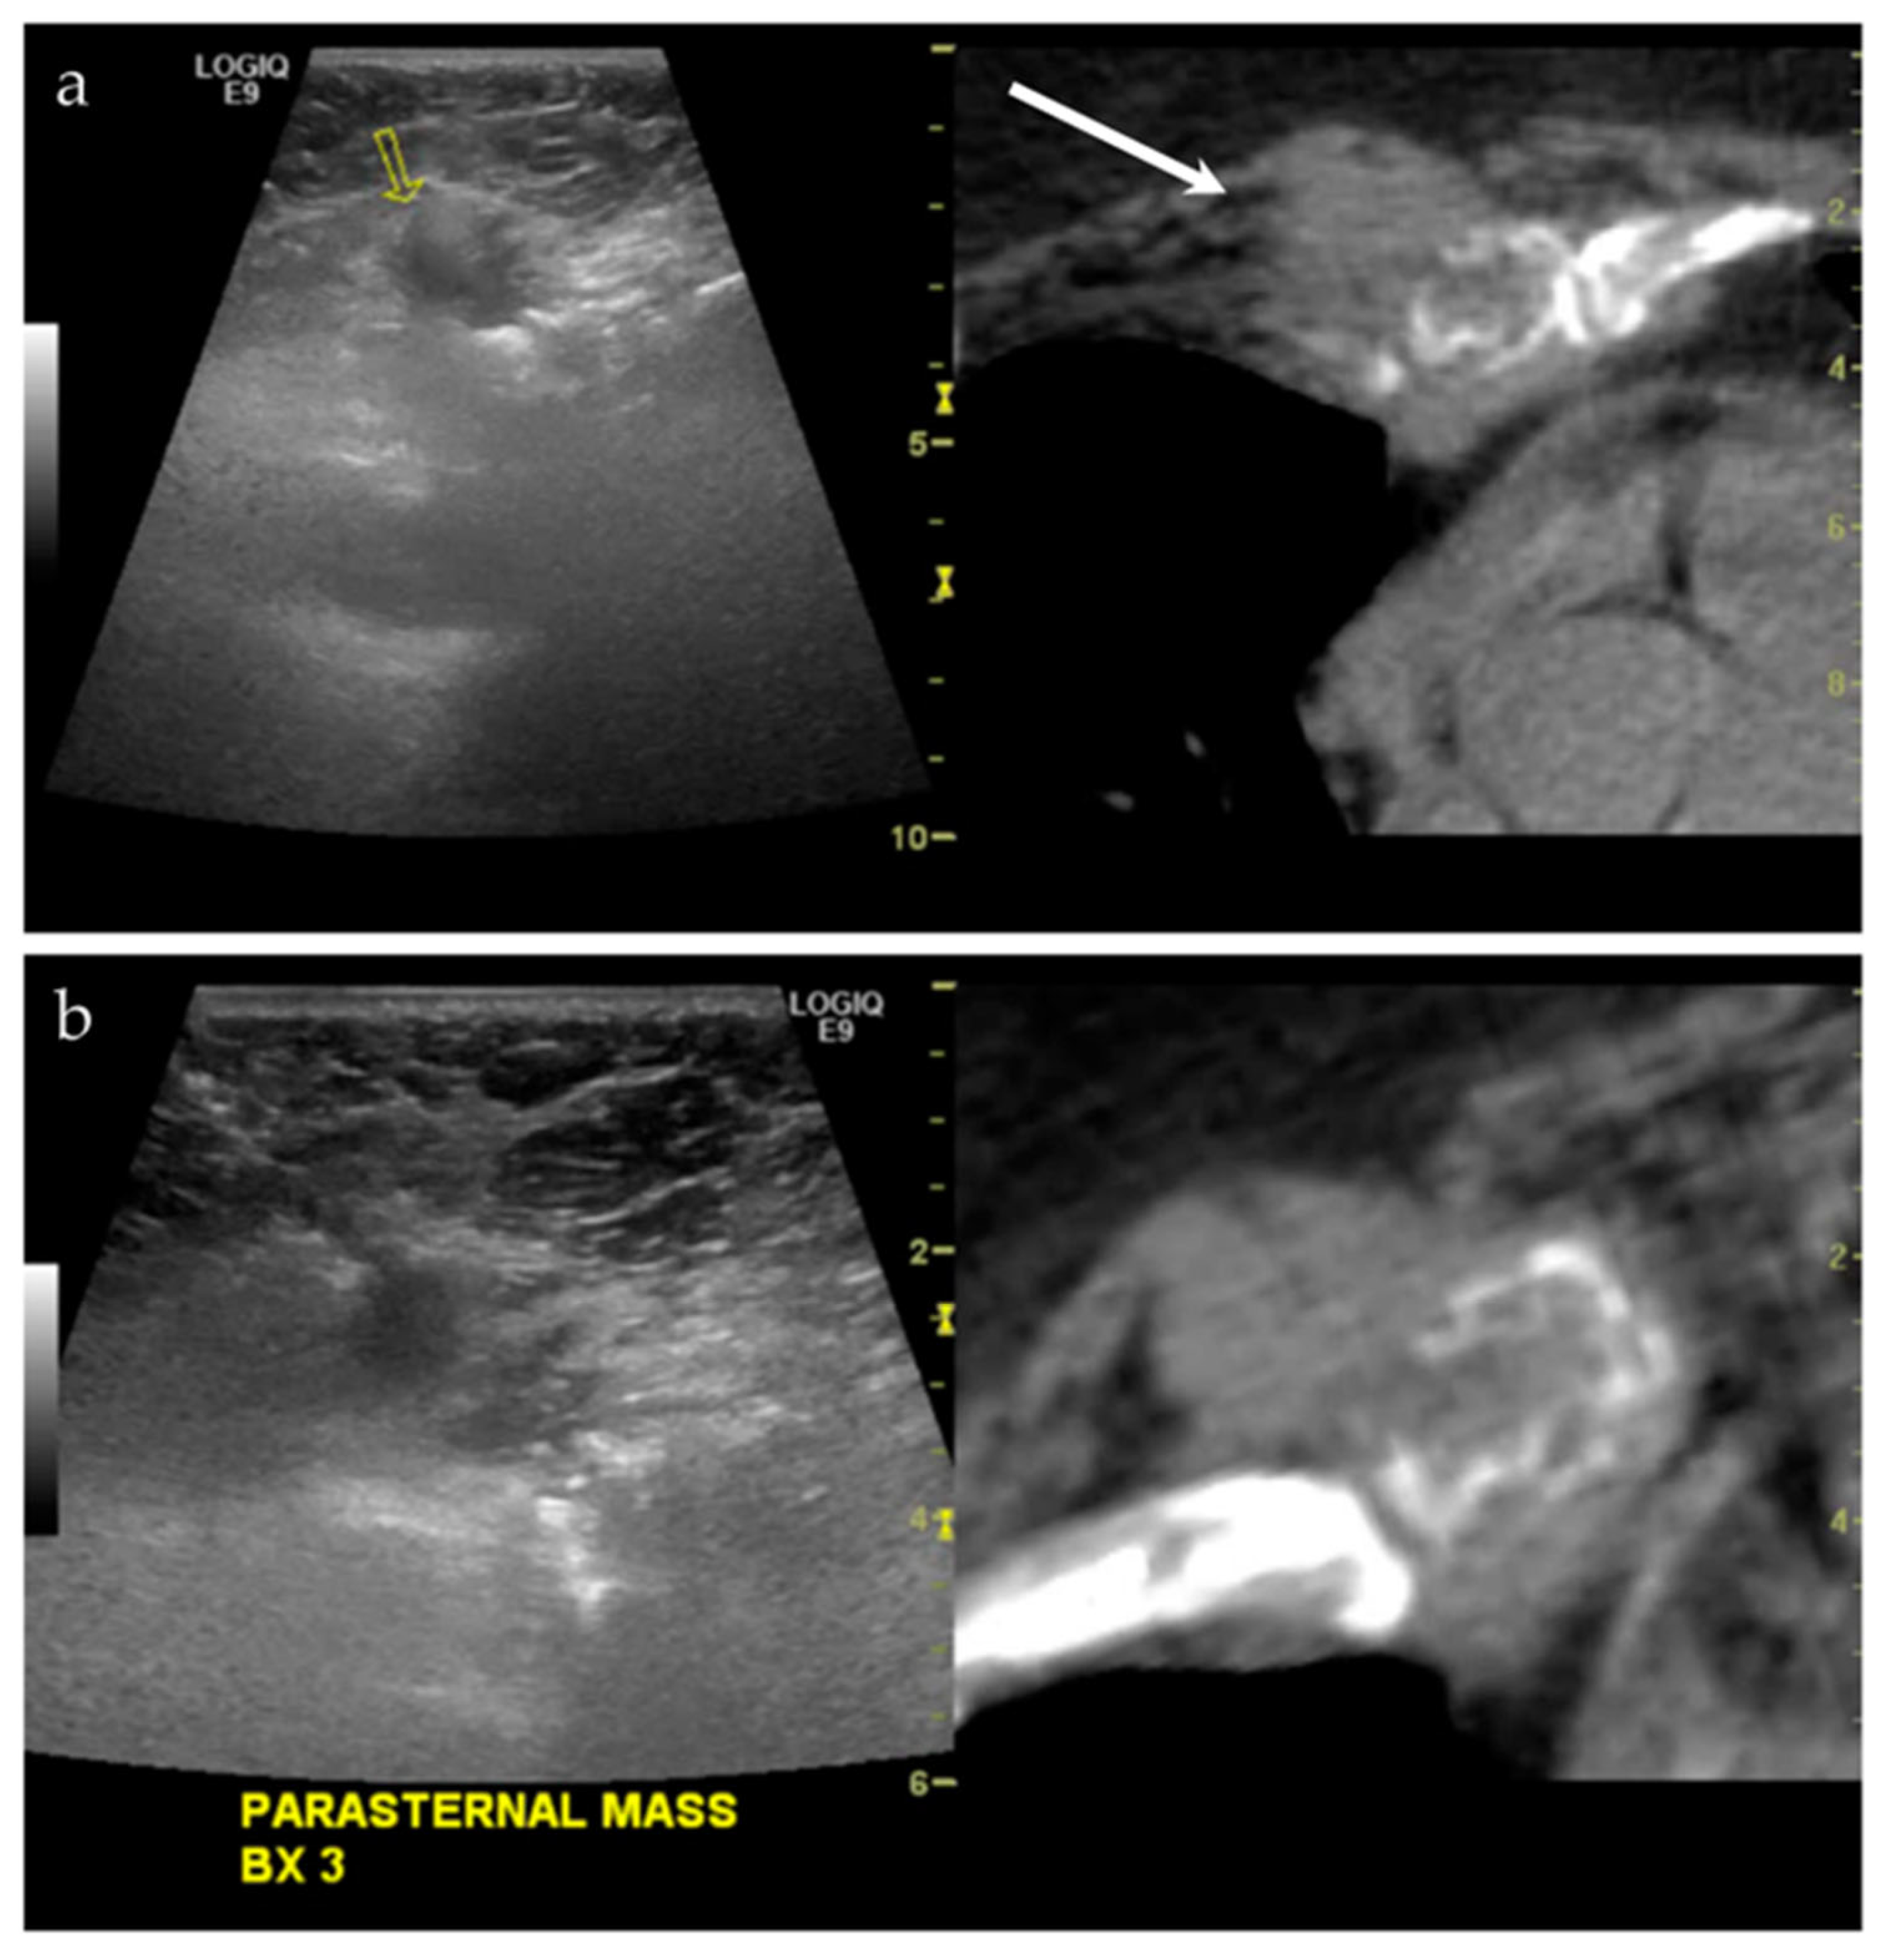

3.2.4. Targeted Percutaneous Lesion Biopsy and/or Aspiration

| 17/M | Acromioclavicular joint | US-MRI | Metastatic disease, nasopharyngeal carcinoma | Neoplastic, malignant |

| 45/M | Right acromion | US-MRI | Epithelioid hemangioma | Neoplastic, benign |

| 18/F | Left posterior knee | US-MRI | Parosteal osteosarcoma, with a chondroblastic component | Neoplastic, malignant |